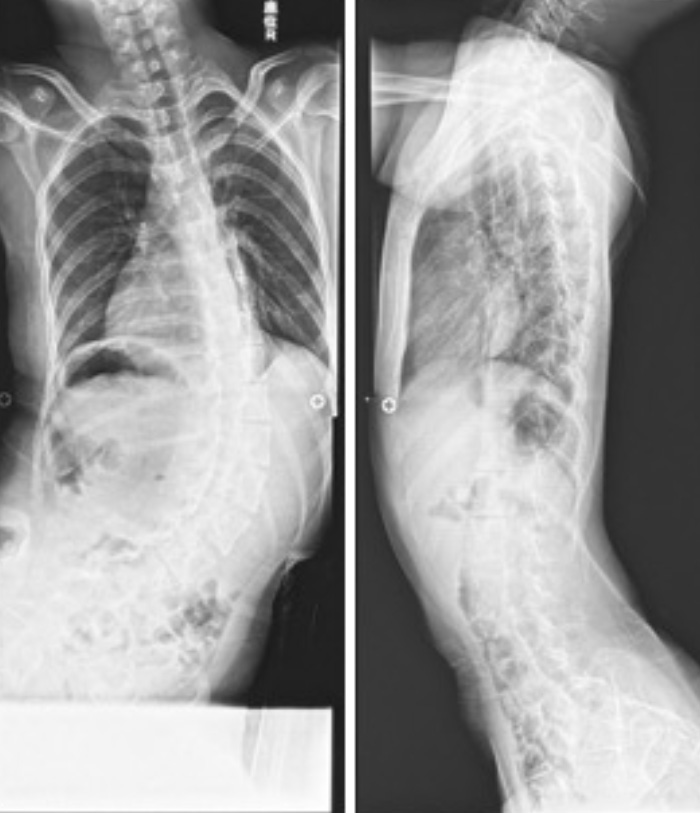

今回は、脳性麻痺による重度運動障害を抱えた方(Hさん)の神経筋原性側弯症(脳性麻痺や筋ジストロフィーといった神経や筋肉の病気に伴う脊柱側弯症)の事例を紹介します。Hさんが側弯を発症するまでの過程と、当時は国内で手術例の少なかった脳性麻痺患者への脊柱側弯症手術に19歳で踏み切るに至るまでの背景、そして手術後の充実した生活までを追います。神経や筋肉の病気を持つお子さんは、身体の成長にともなって側弯症を発症するケースが非常に多く、神経筋原性側弯症とよばれる高度脊柱変形が、呼吸機能障害や消化管機能障害を引き起こすことも少なくありません。そのため、側弯症状の進行を少しでも止めることが重要ですが、Hさんは手術による改善を強く望みました。Hさんが通院する病院では当時は前例のない手術でしたが、その手術によってHさんは「人生が変わった」と言います。そのエピソードをHさんご本人へのインタビューで紐解きます。

Hさん:小学5年生、11歳の頃です。脳性麻痺の子どもは、成長とともに神経筋原性側弯症になることが多いという話は聞いていました。就学前に股関節脱臼の手術を受けて経過観察のために整形外科を受診していたのですが、やはり側弯の症状が進行していると言われていました。私は四肢麻痺ですが、左手だけは意識して力を入れることでなんとか少しだけ動かせるんですね。電動車いすの操作を練習していると無意識のうちに体中にすごく力が入ってしまい、それも側弯が進行した原因のひとつだったと思うのですが、どんどん脊柱の変形が進んでしまいました。車椅子に体幹ベルトで固定してもらっていても、すぐに横に倒れてしまうようになってきて、それでコルセットを装着するようになりました。

Hさん:少しでも側弯の進行を抑えられたらという思いで、小学6年生の時に、かかっていた病院で背中の筋解離手術を受けました。股関節の筋解離手術でもお世話になった先生だったのですが、側弯が進みすぎていたのか、背中の手術にはあまり効果を感じられず、コルセットを外して生活するようになることも叶いませんでした。その後、中学に上がる年齢になって、養護学校を併設している病院に通うようになったのですが、そこで、のちに側弯症の手術を担当してくださるN先生と出会いました。思えば、そのN先生との出会いが私の人生を大きく変えました。

Hさん:その病院だけでなく、全国的に見ても積極的に行っている施設は限られる手術のようでした。背中の側弯となると筋解離手術ではなく、「骨切り手術になるでしょう」ということで、「やるならチタン合金を脊柱に沿わせる手術をするしかない」ということでした。母はそれを聞いて、「無理に手術をしなくても」と言っていましたが、私はどんなにリスクがあっても、前例のない手術でも、どうしても受けたいと思ったので「お願いします」と、N先生に迷いなく言いました。私は先生を信頼していましたし、正直になんでも話してくれるN先生にどうしてもお願いしたかったんです。ただ、先生は必ずしも側弯症の専門でもなかったですし、その場ですぐに「やろう」とは言っていただけませんでした。